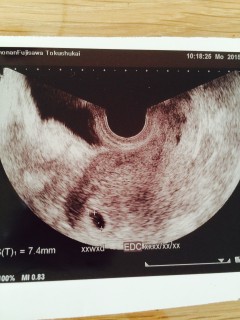

7.4ミリの胎嚢さん^^ 6週目くらいかな?と思い病院に行きましたが、排卵が遅れていたようで、先生には「5週目くらい」と言われました。 次は2週間後に受診です。 心拍まで確認出来るといいな…。 赤ちゃん一緒に頑張ろうね!